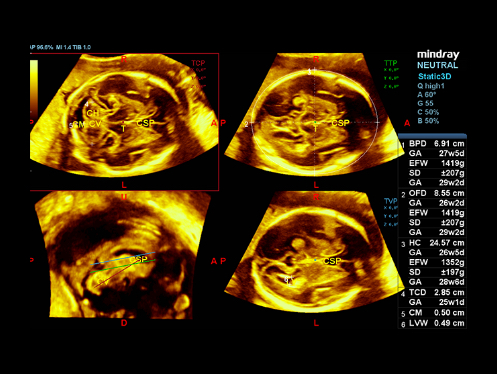

W aparacie DC-80A X-Insight zintegrowano inteligentne rozwi?zania z profesjonalnymi narz?dziami diagnostycznymi w ró?nych aplikacjach i podczas ca?ego cyklu badań: od pocz?tku ci??y, poprzez badania prenatalne, a? po opiek? poporodow?.

Obrazy kliniczne